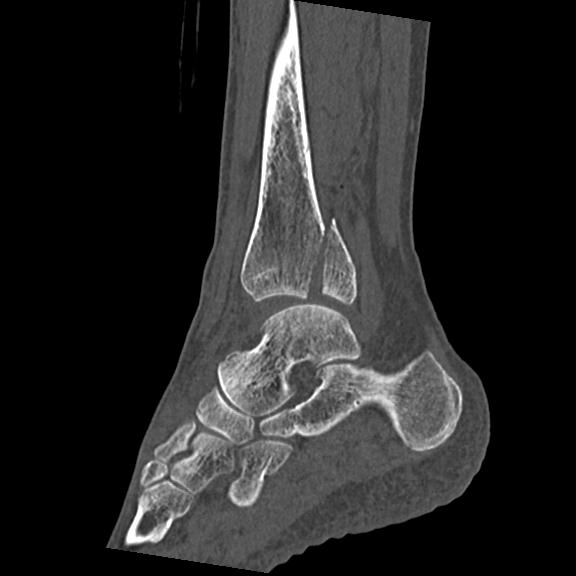

56476 8/28 4R 1/21 2R 左足関節 デジカメ写真 72歳女性 右足関節AS